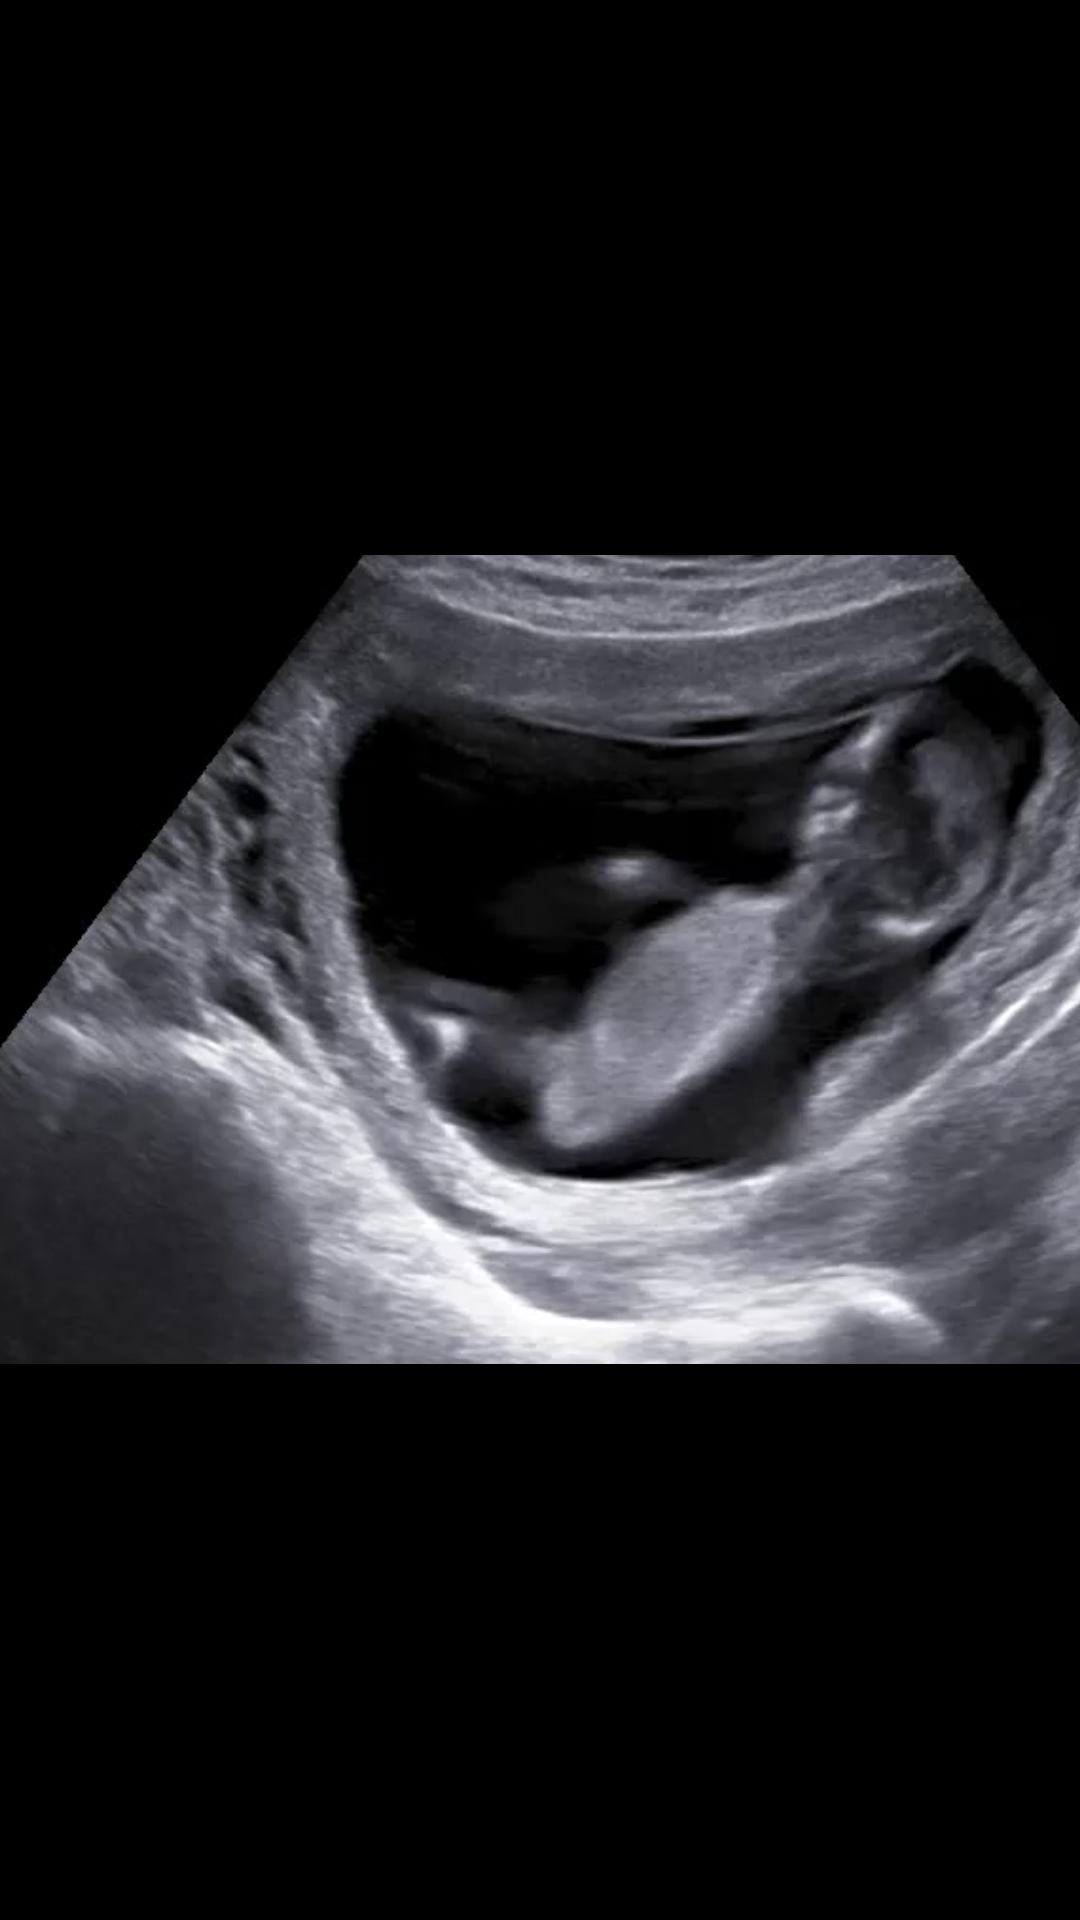

Bu iki fotoyada yorum alabilirmiyim bir arkadaşımın bebeği çok merak ediyor yüklememi istedi

Ekli dosyalar

• Screenshot_20170815-105046.png

Screenshot_20170815-105046.png

885,3 KB · Görüntüleme: 565

• Screenshot_20170815-105502.png

Screenshot_20170815-105502.png

598,1 KB · Görüntüleme: 554

Merhaba, görselde nub çıkıntısı görülmüyor. Ayrıca bu haftalarda cinsiyet tahmini hekimlerin çoğu yapmaz çünkü yanıltıcı olabilir. Bebeğinizin cinsiyetini net olarak 20. haftadan itibaren öğrenebilirsiniz.